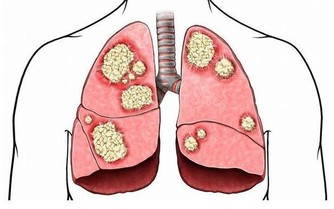

頸椎病:引起手麻最常見的疾病就是頸椎病,它是中 老年人常發的疾病之一。

當人步入中年以後,隨著年齡的增加,

一些器官往往會發生退行性變,當頸椎間盤發生退行性變以後,

往往會導致頸椎間盤突出或是關節突 發生增生或肥大,

這些突出的頸椎間盤或增生的關節突一旦壓迫鄰近的頸神經根時,

便出現了頸椎病。

頸椎病除了有手指麻木、感覺異常以外,還伴隨其它症狀,

如:頸肩部肌肉酸痛,上肢有放射痛或活動障礙等。